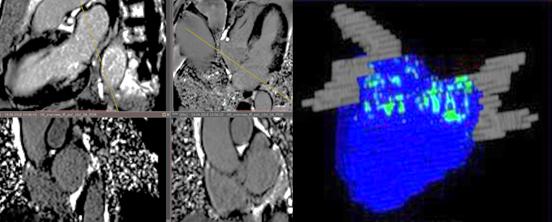

Помимо общего клинического обследования, ЭКГ в 12 стандартных отведениях, эхокардиографию Эхо КГ, всем пациентам проводилась МСКТ коронарография с трехмерной реконструкцией левого предсердия и легочных вен на широкодетекторном КТ томографе PHILIPSINGENITY 128 с использованием ретроспективного мультифазного ЭКГ-синхронизированного протокола сбора данных. Протокол включал получение топограммы органов грудной клетки (ОГК), нативного протокола сбора данных — коронарный кальциевый индекс (ККИ) с подсчетом кальциноза коронарных артерий и аорты по шкале AgatstonScore, ангиографию с использованием автоматического двухколбового шприц-инжектора методикой “BolusTracking” на нисходящий грудной отдел аорты, реконструкцией в фазу 75 % R-Rинтервала сердечного цикла, толщиной среза 0.7 см. Использовался пакет программ мультипланарной реконструкцией коронарного русла: трехмерной реконструкции (3D volumerendering) сердца, построения криволинейных реконструкций через центральную ось коронарных артерий, методики vesselview — изображение артерии, вытянутое в прямую линию с генерацией серии аксиальных срезов коронарных артерий. Оценивались максимальный и минимальный объем ЛП в диастолу и систолу ЛЖ, рассчитывался показатель предсердного вклада в функцию ЛЖ как отношению ударного объема ЛП (УО) к конечно-систолическому объему (КСО) ЛП, на реконструкциях в проекции максимальной интенсивности сигнала (MIP) оценивалась анатомия, количество и размеры легочных вен. Подсчитывались диаметр ЛП, индексированные диастолический и систолический объемы ЛП с учетом объема ушка ЛП (рис. 2).

Рис. 2. Методика объемного моделирования полости ЛП для расчета объема

Fig. 2. Technique of 3D modeling of LA cavity for volume calculation